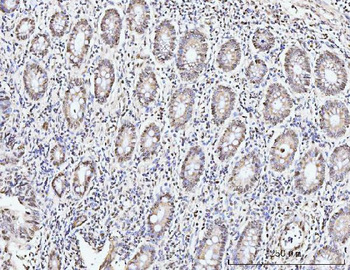

100 μl, 50 μl, 200 μl - ATF4 Recombinant Rabbit Monoclonal Antibody [orb704304]Featured

FC, ICC, IF, IHC-Fr, IHC-P, WB

Human

Mouse

Rabbit

Recombinant

Unconjugated

50 μl, 100 μl - MARK3 Recombinant Rabbit Monoclonal Antibody [orb704310]Featured